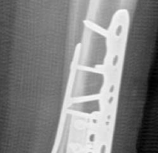

Fig 2.2-5 Intraoperative images.

1. Posterior, anterolateral, and medial plates have been applied. Anatomical reduction and stable fixation of the tibial plafond articular surface has been successfully achieved. At this stage, the fibula had not yet been fixed.

2. Lateral image shows a well-reduced tibial articular surface and a congruent tibiotalar joint.